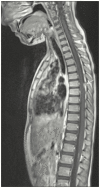

A 7-year-old child of Turkish origin presented with headache and vomiting in the context of prolonged fever of unknown source. At examination, oral candidiasis and chronic onychomycosis were noted. A Candida meningoencephalitis was diagnosed and intravenous Amphotericin B liposomal was given during 6 months relayed by oral Fluconazole after regression of CNS lesions was observed on MRI. A complete immune evaluation was performed, and genetic analysis detected homozygous CARD9 mutation. CARD9 deficiency have been associated with invasive candidiasis in otherwise healthy patients. Culture of the cerebrospinal fluid grew for multisensitive Candida albicans. Brain magnetic resonance (MRI) showed the presence of focal lesions in the left caudate nucleus and in the right cerebellar hemisphere. Medullar MRI showed diffuse meningeal nodular lesions. Treatment with intravenous amphotericin B liposomal was given during 6 months relayed by oral fluconazole after regression of CNS lesions was observed on MRI. A complete immune evaluation was performed and genetic analysis detected a homozygous CARD9 mutation. CARD9 deficiency have been associated with invasive candidiasis in otherwise healthy patients.